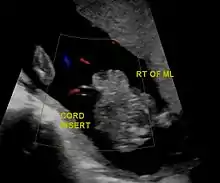

| Diagnostic method | Ultrasound during pregnancy, based on symptom at birth[1] |

In the developed world, around 90% of cases are identified during normal ultrasound screens, usually in the second trimester.[17]